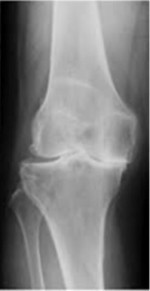

年代ごとの変形の進み具合

左が若い年代で右にいけばいくほど変形が進んでいる

右側は変形が進み『手術』という言葉が選択肢として出てくる。